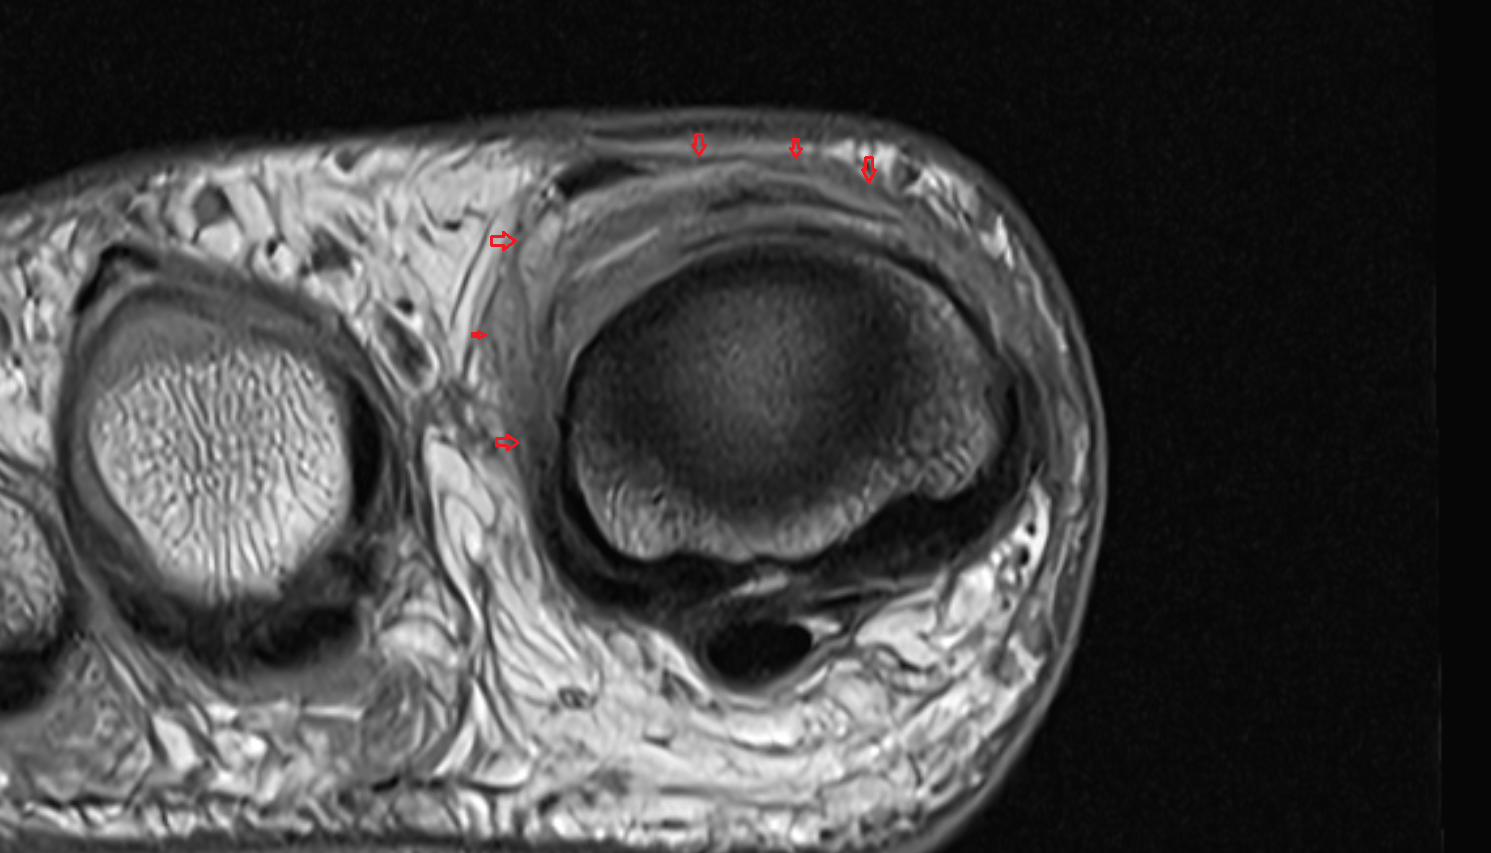

- Peripheral zone of prostate

- Anterior Fibromuscular Stroma of prostate

- Central zone of prostate

- Transitional zone of prostate